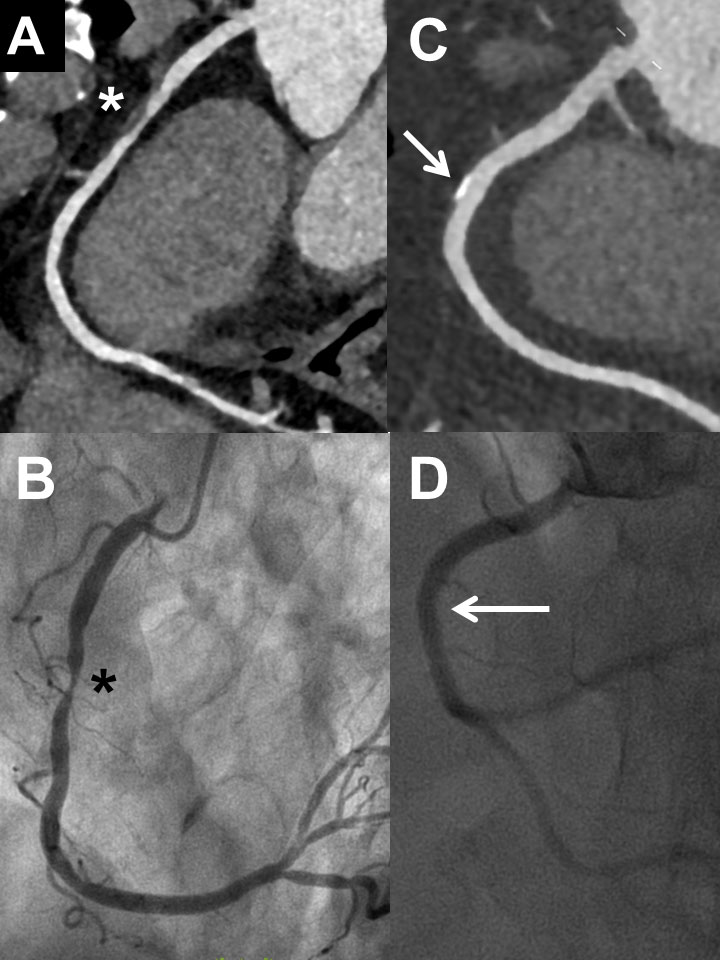

As shown in table 2 and figure 1, not all patients undergoing invasive coronary angiography had coronary artery disease by CCTA. However, invasive coronary angiography identified coronary artery disease in a high proportion of patients in all pretest probability groups (between 67 and 88%): there were 47 patients with coronary artery disease by invasive coronary angiography, 36 of whom underwent revascularisation. Notably, there were 14 patients with pretest probability <15% in whom invasive coronary angiography demonstrated coronary artery disease and nine out of these 14 patients underwent coronary revascularisation. Detailed findings of CCTA and invasive coronary angiography in the 59 patients who underwent both tests are shown in supplementary table S1 in appendix 1. In figures 2 and 3 , some representative examples of CCTA and invasive coronary angiography are shown.

Figure 2 Examples of coronary computed tomography (CCTA) and invasive coronary angiography (ICA) in two patients with excellent correlation of the two methods: First patient (male, 62 years) with severe stenosis in the mid right coronary artery in CCTA (panel A, asterisk) and ICA (panel B, asterisk). Second patient (male, 58 years) with plaque (no relevant stenosis) in the mid right coronary artery in CCTA (panel C, arrow) and ICA (panel D, arrow).